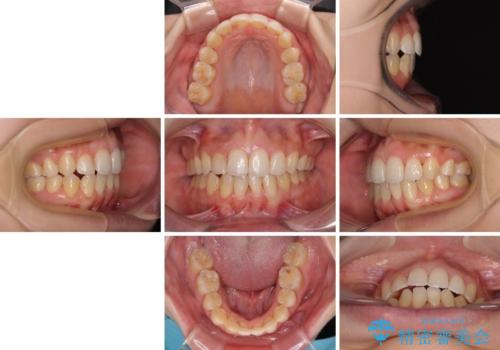

詰め物で隠していた下顎前歯の隙間は、歯軸を改善することで詰め物を除去しても隙間が目立たなくなりました。

まだ改善したいところはありましたが、患者様自身は大変満足されたとのことで、治療を終えることとなりました。